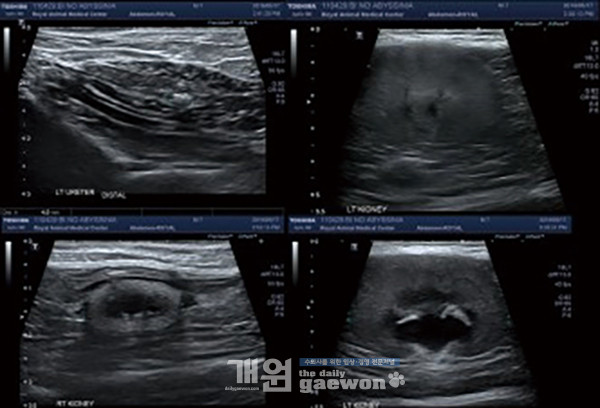

환자의 임상병리 검사는 BUN(248.4 mg/dl), Creatine(17.1 mg/dl)로서 IRIS stage IV로 고려됩니다. 왼쪽 신장도 감염이나 신부전이 의심됩니다. Mildly decreased peritoneal contrast adjacent to Lt. kidney(retroperitoneal space): focal peritonitis, mild peritoneal effusion가 초음파 검사상 관찰됩니다(그림 8).

Kidney & urinary tract, Left kidney에서 좌측 renal length는 5.3cm 정도로 크게 관찰됩니다. Renal cortex는 hyperechoic하게 관찰되었고, corticomedullary definition이 indistinct하게 관찰됩니다.

renal pelvis는 1cm 정도로 severe하게 dilation되어 관찰됩니다. 좌측 ureter는 2mm 미만의 dilation으로 관찰됩니다.

Uretero-vesical junction 위치로 4mm 정도 크기의 acoustic shadowing을 동반하는 mineralization 음영이 관찰됩니다.

좌측 신장 caudal 측면으로 retro-peritoneal fat echogenicity는 증가되어 관찰되었고, 소량의 free fluid가 동반되어 관찰됩니다(그림 9).

RI index는 8.3 정도로 측정됩니다. 위 환자는 왼쪽 신장에 SUB의 장착을 실시하였습니다(그림 10).